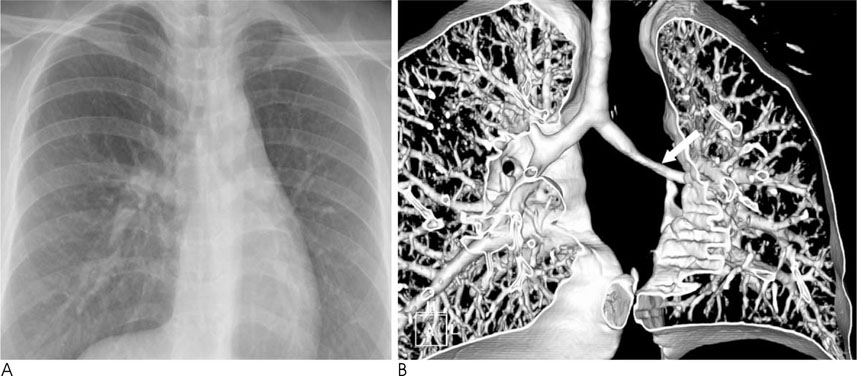

Tracheobronchial Branching Anomalies

- There are various congenital anomalies with respect to the number, length, diameter, and location of tracheobronchial branching patterns. The tracheobronchial anomalies are classified into two groups. The first one, anomalies of division, includes tracheal bronchus, cardiac bronchus, tracheal diverticulum, pulmonary isomerism, and minor variations. The second one, dysmorphic lung, includes lung agenesis-hypoplasia complex and lobar agenesis-aplasia complex.